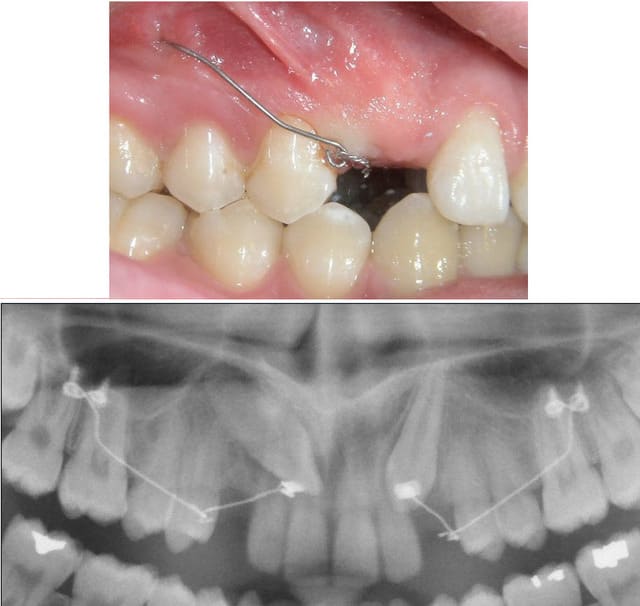

Je vois une patiente de 15 ans dans le cadre de MTDents. Je constate que 13 et 23 sont absentes avec 13 que l'on arrive à palper sous la gencive.

Le problème, c'est qu'il n'y a pas du tout de place pour 13 et 23 puisque 12/14 et 22/24 sont en continuité.

J'attends la pano pour objectiver 13 et 23 : 13 au moins est présente, on peut la palper au niveau de la gencive.

je suis ortho, l'agénésie des canines est excessivement rare, il s'agit certainement d'une rétention des dents par manque de place, voire de dents incluses. La bonne atttitude est évidemment d'effectuer un examen radiologique et ensuite d'adresser la patiente à un ortho. Même si le patient ne veut pas faire de traitement, au moins il aura reçu toutes les informations. L'extraction des canines n'est certainement pas la bonne décision.

Ct8 1 - Eugenol